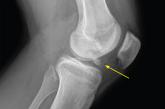

Knee pain and injury: When is a surgical consult needed?

This review identifies clinical scenarios—such as unstable or displaced fractures, major tendon ruptures, and significant mechanical issues—that...